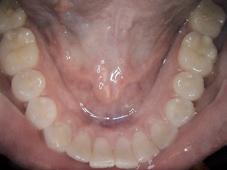

Har du god nok dokumentasjon? Undersøkelse fra Helfo viser at overraskende mange tannleger ikke har tilstrekkelig dokumentasjon, noe man er pålagt. Det kan koste deg dyrt! Med et intraoralt kamera kan du enkelt ta flotte nærbilder, som kan lagres eller skrives ut.

Dokumentér dine funn

Bilder er en viktig del av journalen, og ofte eneste dokumentasjon for dine funn.

Det forutsettes at tannlege eller tannpleier har innhentet nødvendig dokumentasjon før stønadsberettiget behandling starter. Det vises til helsepersonelloven med tilhørende forskrifter. Der det er nødvendig av kontrollhensyn, vil Helfo be tannlege/tannpleier eller bruker om å fremlegge nødvendig dokumentasjon på at behandlingen var stønadsberettiget. Eksempel på hva som kan være aktuell dokumentasjon er legeerklæring, kopi av aktuelle deler av pasientjournalen, røntgenbilder, foto og prøvesvar.

Det fremgår av helsepersonelloven at den som yter helsehjelp, skal nedtegne eller registrere opplysninger i en journal for den enkelte pasient. Journalen skal føres i samsvar med god yrkesskikk og skal inneholde relevante og nødvendige opplysninger om pasienten og helsehjelpen, samt de opplysninger som er nødvendige for å oppfylle meldeplikt eller opplysningsplikt fastsatt i lov eller i medhold av lov. Journalen skal være lett å forstå for annet kvalifisert helsepersonell. Det skal videre fremgå hvem som har ført opplysningene i journalen. Departementet har i forskrift 21. desember 2000 nr.1385 om pasientjournal (journalforskriften) gitt nærmere regler om pasientjournalens innhold og ansvar for journalen. Journalen skal først og fremst være et redskap for å sikre at pasientene får forsvarlig helsehjelp, men journalen vil også kunne ha betydning i forbindelse med eventuelle tilsynssaker og erstatningssaker for feilbehandling.

Journalen skal inneholde opplysninger som er relevante og nødvendige. Den skal blant annet inneholde foreløpig diagnose, observasjoner, funn, undersøkelser, plan eller avtale om videre oppfølging. Når det settes i verk behandlingstiltak som fraviker gjeldende retningslinjer er det et særlig behov for å dokumentere hvorfor slik behandling er iverksatt. Av journalen skal det derfor fremgå at tiltaket fraviker retningslinjene og hvilke overveielser som har ledet frem til bruk av et slikt tiltak. Videre bør det fremgå av journalen at pasienten er gitt den informasjon som er nødvendig for å gi pasienten et tilstrekkelig informasjonsgrunnlag for å samtykke til eller avslå den aktuelle undersøkelse eller behandling.

Helfo kan avslå krav om stønad når stønadsretten ikke er dokumentert, og de kan også kreve tilbake utbetalt stønad i forbindelse med etterfølgende kontroll. God journalføring er også viktig ved henvisning av pasient til andre behandlere. Hvis undersøkelse, diagnostikk og behandling er godt beskrevet og dokumentert i journalen, kan det bidra til at man unngår dobbeltbehandling eller i verste fall feilbehandling. God journalføring øker pasientsikkerheten.